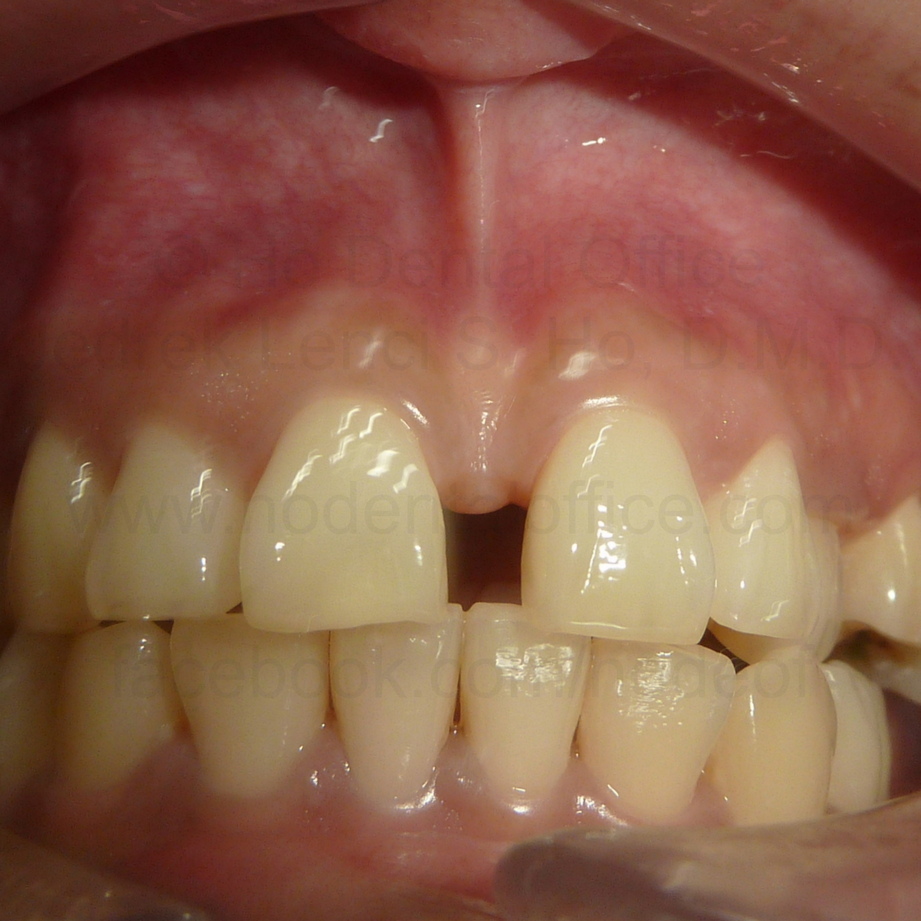

Patient came in for prophylaxis and orthodontic consultation on March 2017. Her chief complaint was the big gap in the middle of her two incisors.

Upon observation, a very big frenum attachment is evident, with the "pull" of the muscle fibers (seen while stretching the lips) reaching all the way up to the incisive papilla on the back of the upper incisors. Patient was also checked with x-ray to ascertain presence of impacted teeth, if any.

Since the cause of the diastema (big gap in the middle) was determined to be not caused by a hidden impacted tooth, it is highly likely that the strong frenum muscle attachment was the one causing it, as there have been documented cases similar to this that can be seen on dental textbooks and scientific papers.